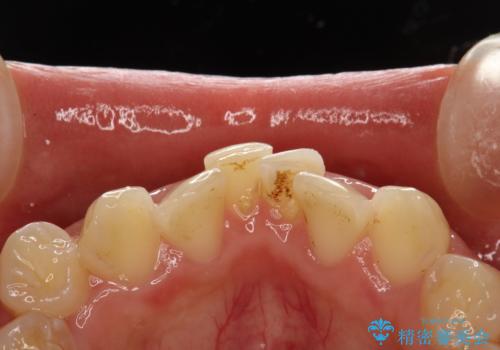

- 矯正治療前にステインを取りたいとのことで来院されました。ステインは前歯のみだったため、PMTC30分コースを行いました。

PMTCとは、歯科の専門家が器械を使用して行う歯のクリーニングのことです。普段の歯磨きでは取り切れない溝、キワなどの細かい部分も徹底的に除去します。ステインや歯石などが付着したままだと、虫歯や歯周病の発見がしずらいことがあります。特に矯正治療前には、念入りな虫歯や歯周病チェックが必要なため、PMTCでしっかりと汚れを除去しておくことが大切です。